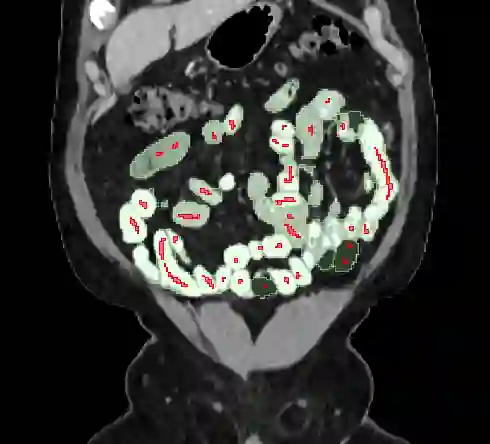

We present a novel graph-theoretic method for small bowel path tracking. It is formulated as finding the minimum cost path between given start and end nodes on a graph that is constructed based on the bowel wall detection. We observed that a trivial solution with many short-cuts is easily made even with the wall detection, where the tracked path penetrates indistinct walls around the contact between different parts of the small bowel. Thus, we propose to include must-pass nodes in finding the path to better cover the entire course of the small bowel. The proposed method does not entail training with ground-truth paths while the previous methods do. We acquired ground-truth paths that are all connected from start to end of the small bowel for 10 abdominal CT scans, which enables the evaluation of the path tracking for the entire course of the small bowel. The proposed method showed clear improvements in terms of several metrics compared to the baseline method. The maximum length of the path that is tracked without an error per scan, by the proposed method, is above 800mm on average.